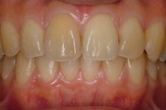

CASE3

前歯1本だけが出ています、矯正で治りますか?

(23歳/女性)↓

||||||||

概要・担当医コメント:

前歯の唇側傾斜/マルチブラケット装置/非抜歯

動的治療期間15ヶ月(15回)/費用概算:60万円.

歯列アーチの形態修正に必要なスペースを微量のエナメル質の研磨により創生し,当初の計画通りに歯を移動させました.